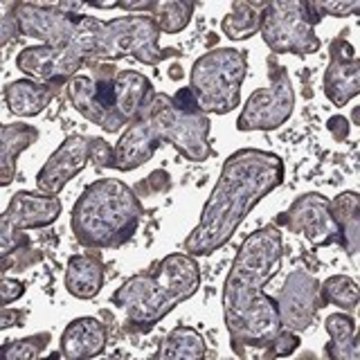

Anti-FLT4 antibody produced in rabbit

PCL, VEGFR3, Anti-FLT41 antibody produced in rabbit, Anti-LMPH1A antibody produced in rabbit, Anti-PCL antibody produced in rabbit, Anti-VEGFR3 antibody produced in rabbit, Anti-fms-related tyrosine kinase 4 antibody produced in rabbit